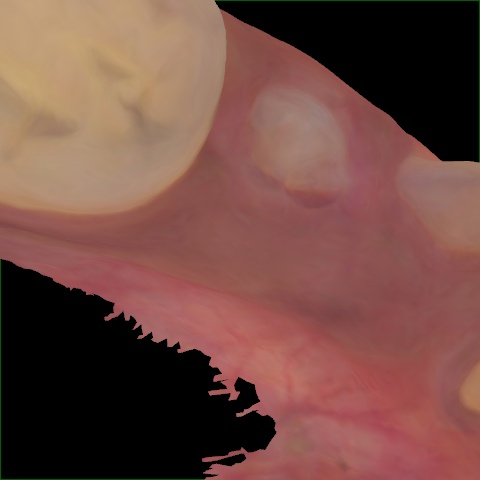

NHD25470

Annotated as "Good"

Original Image Rendering Image